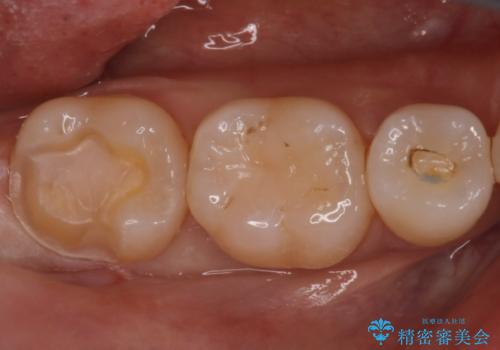

- 昔に治療した金属のかぶせものが取れてしまい来院されました。他院にて応急処置がされており、レントゲンなどで現状を把握した後、切削量が比較的少なく短期間で終了するセラミックアンレーにて治療いたしました。

経過良好で噛み合わせなども問題なく、前の被せ物より綺麗な被せ物がセットされ、非常に満足いただけました。